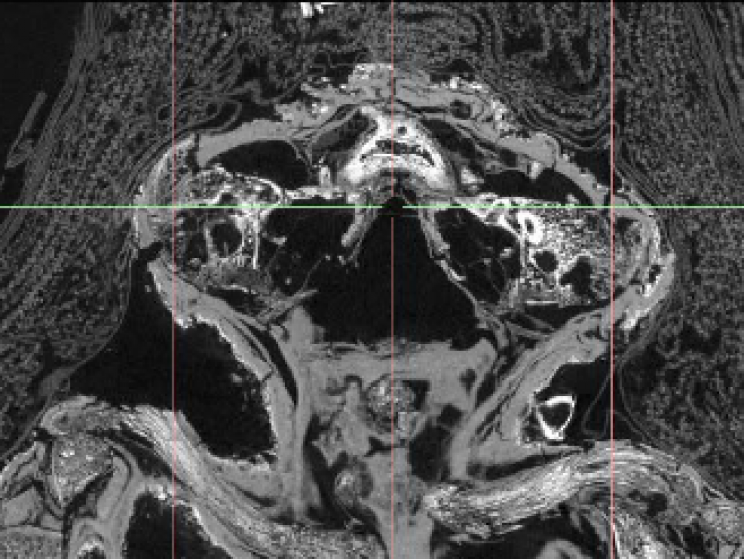

Sự thật chỉ được hé lộ khi Andrew Nelson - nhà khảo cổ sinh vật học và giáo sư ngành nhân chủng học tại Đại học Western Ontario cùng các cộng sự đã thực hiện nghiên cứu xác ướp bằng kỹ thuật chụp cắt lớp vi tính (micro CT scanning) và phát hiện bí mật bất ngờ.

Cụ thể, kết quả kiểm tra cho thấy xác ướp tí hon mà mọi người cứ nghĩ là của diều hâu lại là một đứa trẻ chết yểu khi 23 - 28 tuần tuổi.

Thi hài bé trai này chết non là trường hợp hiếm gặp vì não và hộp sọ cậu bé đã không thể phát triển. Toàn bộ phần đầu hộp sọ đã không được thành hình. Thêm nữa, các đốt sống của cậu bé đã không khít với nhau và tiểu cốt nhĩ lại nằm phía sau đầu.

Theo nhà khảo cổ Nelson, xác ướp bé trai này là một trong 2 xác ướp duy nhất được phát hiện ở Ai Cập mắc phải hội chứng Anencephaly (thiếu một phần não khi sinh).